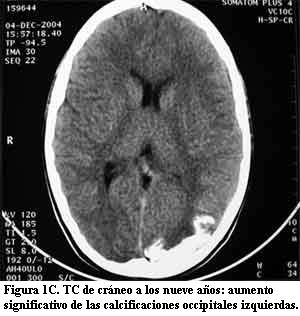

Niña de 10 años, sin antecedentes pre ni perinatales que a los 10 meses de edad, luego de un traumatismo de cráneo de intensidad leve, presentó crisis caracterizadas por vómitos, desviación óculo-cefálica a izquierda e hipotonía global, con sopor posterior, que se reiteraron en el curso de 24 horas. Su examen físico fue normal. En esa oportunidad se le realizó fondo de ojo, tomografía de cráneo (TC) (figura 1A) y electroencefalograma (EEG), que fueron normales. Evolucionó favorablemente hasta la edad de 4 años, cuando presentó nuevamente crisis epilépticas parciales complejas, con un episodio de status epilepticus. El EEG mostró signos de sufrimiento cerebral focal a nivel parieto-occipital izquierdo. En la TC se observó una imagen hiperdensa occipital izquierda (figura 1B). La resonancia magnética (RM) mostró un área de realce leptomeníngeo con el gadolinium en la misma topografía en relación con una corteza cerebral de aspecto atrófico, así como el plexo coroideo ipsilateral aumentado de tamaño (figura 2). En la angiorresonancia se observó una disminución de la señal de flujo en el seno venoso lateral izquierdo que se interpretó secundaria a trombosis (figura 3A). En la angiografía digital se comprobó que el seno venoso estaba permeable con un marcado enlentecimiento de la circulación compatible con estasis venosa y una alteración de la barrera hematoencefálica a nivel occipital izquierdo (figura 3B). Los anticuerpos antigliadina y antiendomisio fueron negativos. El estudio de los factores de la coagulación descartó una alteración protrombótica. Medicada con difenilhidantoína, reiteró crisis similares a las anteriores a los 6 años de edad. Desde el punto de vista neuropsicológico, su nivel intelectual fue catalogado como marginal. Luego de tres años sin crisis, a los 9 años presentó un episodio de breve duración caracterizado por cefalea intensa y alteración de la conciencia. En la exploración neurológica se comprobó que presentaba una discreta paresia de miembro superior derecho. Una nueva TC mostró un significativo aumento de las calcificaciones occipitales izquierdas (figura 1C).

La presencia de un angioma facial congénito con las características antes mencionadas es el signo principal que orienta hacia el diagnóstico en el SSW clásico (1,3,7,16). Como las otras manifestaciones clínicas pueden ser relativamente inespecíficas, cuando el paciente no presenta las lesiones cutáneas típicas, el diagnóstico de angiomatosis leptomeníngea se basa fundamentalmente en los hallazgos neuroimagenológicos. Las primeras manifestaciones clínicas de este caso clínico fueron sus crisis epilépticas parciales a los 10 meses de edad pero en ese momento, el examen físico y la TC fueron normales. A los 4 años, cuando reiteró crisis epilépticas, se observaron las calcificaciones occipitales izquierdas en una nueva TC. La RM con gadolinium mostró las imágenes típicas de la angiomatosis pial con un área de realce leptomeníngeo a nivel parieto-occipital izquierdo, en relación con una corteza cerebral de aspecto atrófico, así como el plexo coroideo ipsilateral aumentado de tamaño. Se realizó una angiorresonancia en la cual se observó una disminución de la señal de flujo en el seno venoso lateral izquierdo que se interpretó como secundaria a trombosis. Sin embargo, la angiografía digital realizada tres días después, mostró que el seno venoso estaba permeable y que presentaba un marcado enlentecimiento de la circulación compatible con estasis venosa. Posteriormente, a los 9 años, una nueva TC mostró un significativo aumento de las calcificaciones occipitales, persistiendo la imagen del plexo coroideo aumentado de tamaño. Esta serie de estudios imagenológicos es enteramente compatible con el diagnóstico de angiomatosis leptomeníngea (1,6,8,10,13-18).

Existen pocos estudios publicados que describan la evolución clínica e imagenológica de los pacientes con SSW (22). Si bien en la literatura se menciona la progresión de las calcificaciones, no es habitual que la misma se haya documentado como en este caso, desde la tomografía normal obtenida a los 10 meses de vida, a la observación de las calcificaciones a los 4 años y la comprobación del significativo aumento de las mismas a los 9 años de vida. Es interesante destacar la discordancia existente entre la evolución de la epilepsia de esta paciente durante sus primeros 10 años de vida, que ha sido aceptablemente controlada, y la significativa progresión de las lesiones encefálicas objetivadas en el aumento de las calcificaciones en el seguimiento tomográfico.